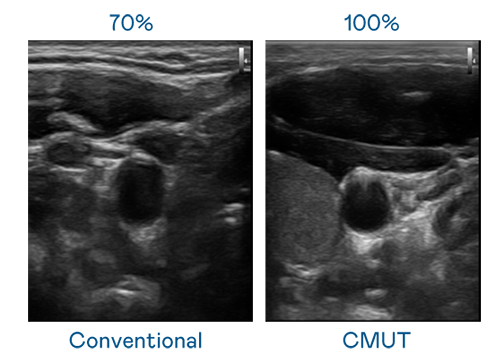

CMUT 技术是一种用电容式微机电元件来产生超音波讯号的技术。与传统 PZT 压电式技术相比,CMUT 频宽增加 30%,更宽频的超音波讯号让影像解析度大幅提升,是实现高影像品质医疗超音波扫描、促进精准医疗发展的关键技术。

超音波影像的解析度高低,首先取决于探头能发出的讯号频宽。开云kaiyun CMUT 可提供高清晰的超音波讯号,提供高频宽、高灵敏度、影像纹理细节更高的超音波影像,协助医护人员缩短影像判读时间及利用精准的医疗影像进行诊断。